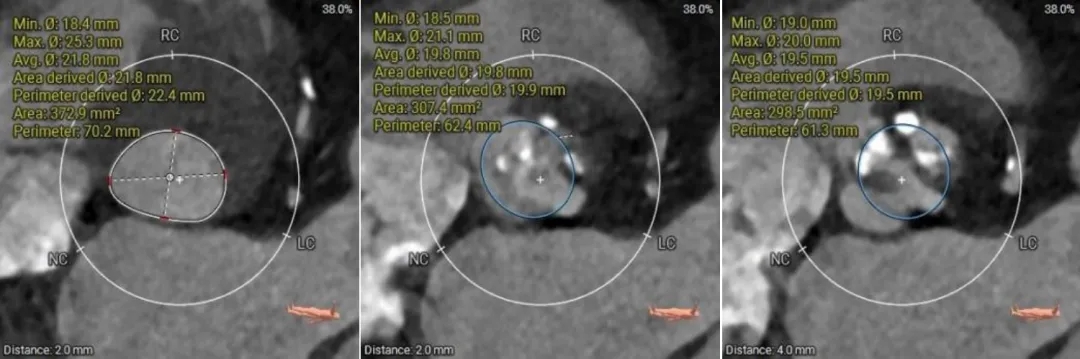

(1)Type 0二叶式主动脉瓣,瓣环适中,中度钙化,Type 0二叶瓣受瓣口形态及钙化影响,瓣架呈非理想椭圆形展开,对瓣架支撑力与顺应性提出了更高要求,同时该病例合并升主扩张,对同轴性和释放的稳定性提出了更高的要求。因此优先选择支撑性和顺应性兼具的瓣膜,以及较柔软花冠的瓣膜,降低对升主动脉的损伤,小锥角的设计进一步提升了瓣膜在释放的稳定性

(2)窦部空间较小,左侧瓣叶冗长,且开口位置在短轴平面,左冠冠脉风险较高,优先选择有收腰设计的瓣膜,降低冠脉风险并保留术后足够的VTC